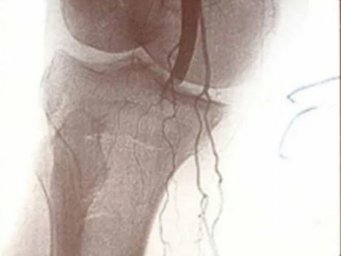

Благодаря уникальным малоинвазивным операциям по эмболизации ветвей подколенной или локтевой артерии, которые проводятся на современном медицинском оборудовании, пациенты избавляются от мучительных болей и возвращаются к активной жизни.

«Эмболизация ветвей локтевой или подколенной артерии является эффективным решением для пациентов, у которых консервативное лечение не принесло желаемого результата. Эта методика часто становится единственным шансом на избавление от болевого синдрома при медиальном эпиконделите, гонартрозе 3 степени и других серьезных заболеваниях костно-двигательной системы», — поясняет врач травматолог-ортопед ГБУЗ «Домодедовская больница» Министерства здравоохранения Московской области Камал Меджидов.